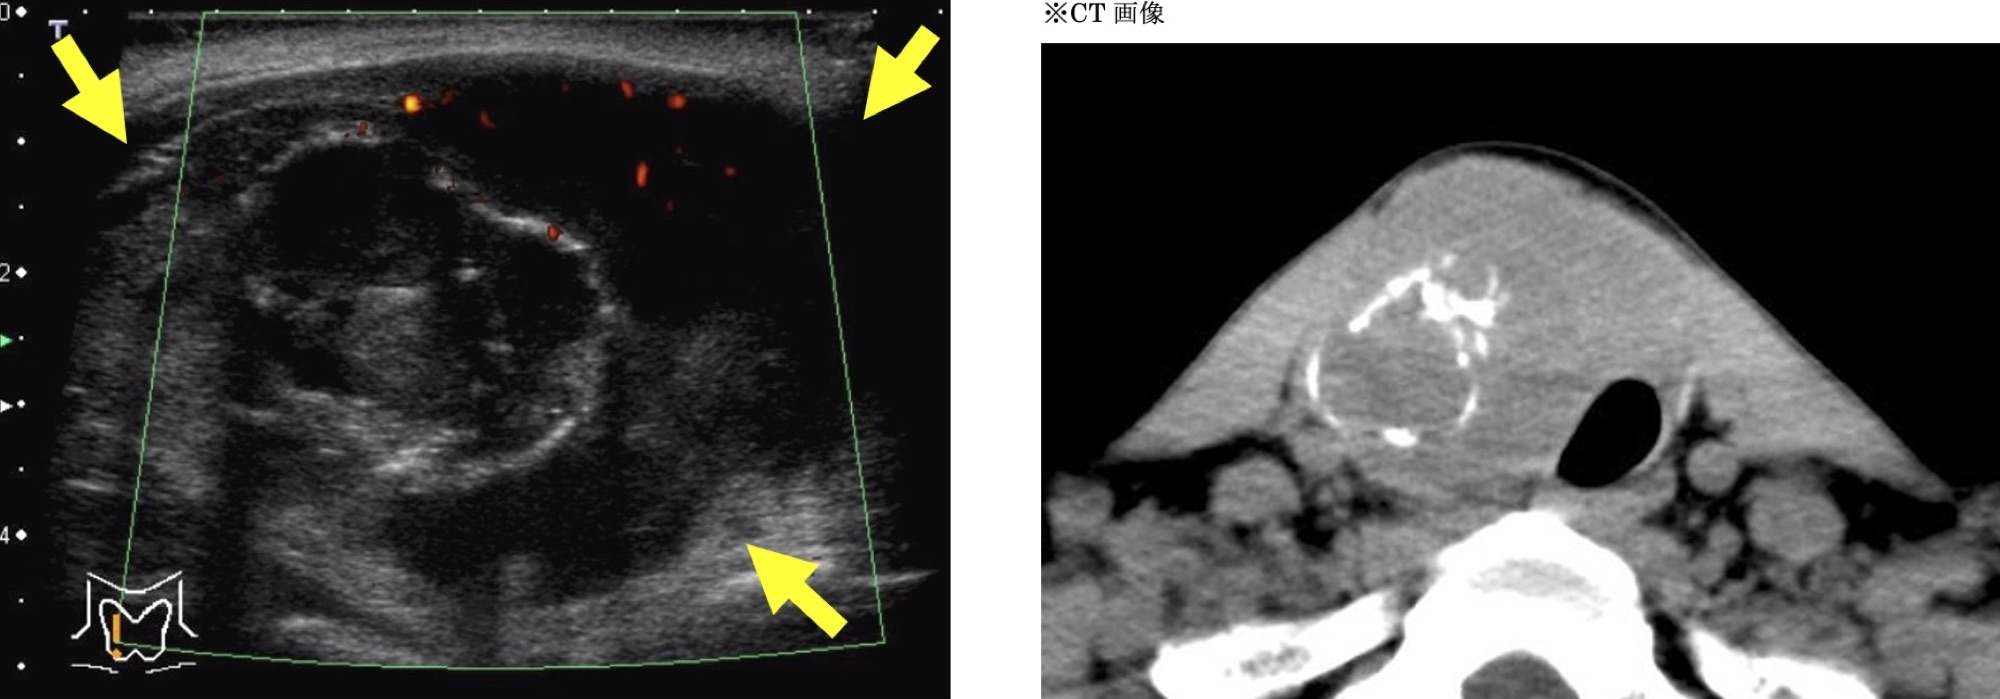

未分化がん

大きな腫瘍で、形がいびつ(形状不整)です。内部に丸い白い部分(卵殻状石灰化)が見られることが多く、以前に腫瘍があった痕跡と考えられています(未分化がんは長期間存在した別の腫瘍(乳頭がんや濾胞がん)から変化すると考えられています)。